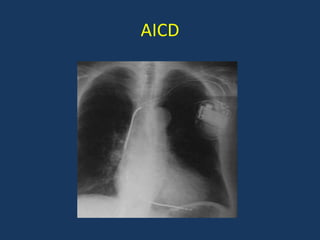

Devices in Heart Failure

• Biventricular Pacing or Cardiac

Resynchronization therapy [CRT]

• Automatic Implantable Cardioverter

Defibrillator[AICD]

Role of AICD in HF

• Prevention of sudden death is an important goal in

HF.

• Approximately half of the deaths in patients with

HF, especially in those with milder symptoms, occur

suddenly and unexpectedly,

• Many, if not most, of these are related to ventricular

arrhythmias

Recommendation for AICD in HF

• Secondary Prevention

– Survivor of SCA or documented VT irrespective of

LVEF

• Primary Prevention

– LVEF<35% and class II-III Symptoms despite 3

months optimal medical therapy

– Post MI LVEF <35% after 40 days

– Post CABG/PCI <35% after 3 months

AICD